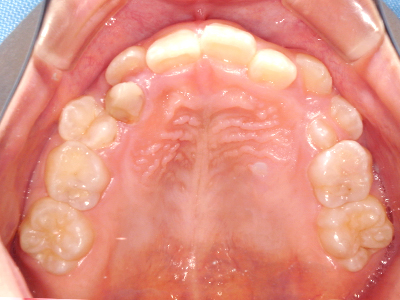

歯並びの相談に来られるお子様は、口呼吸をしているケースが多く、これが歯並びに大きな影響を与えています。

↓ - 頬の圧力が上の歯列にかかりやすくなる

↓ - 上あごが狭くなる

ないき歯科クリニックでは、上あごの成長不足を補い、鼻呼吸を獲得しつつ歯列を整え、将来のお口をより健康な状態にすることをゴールに定める矯正治療をおこなっています。